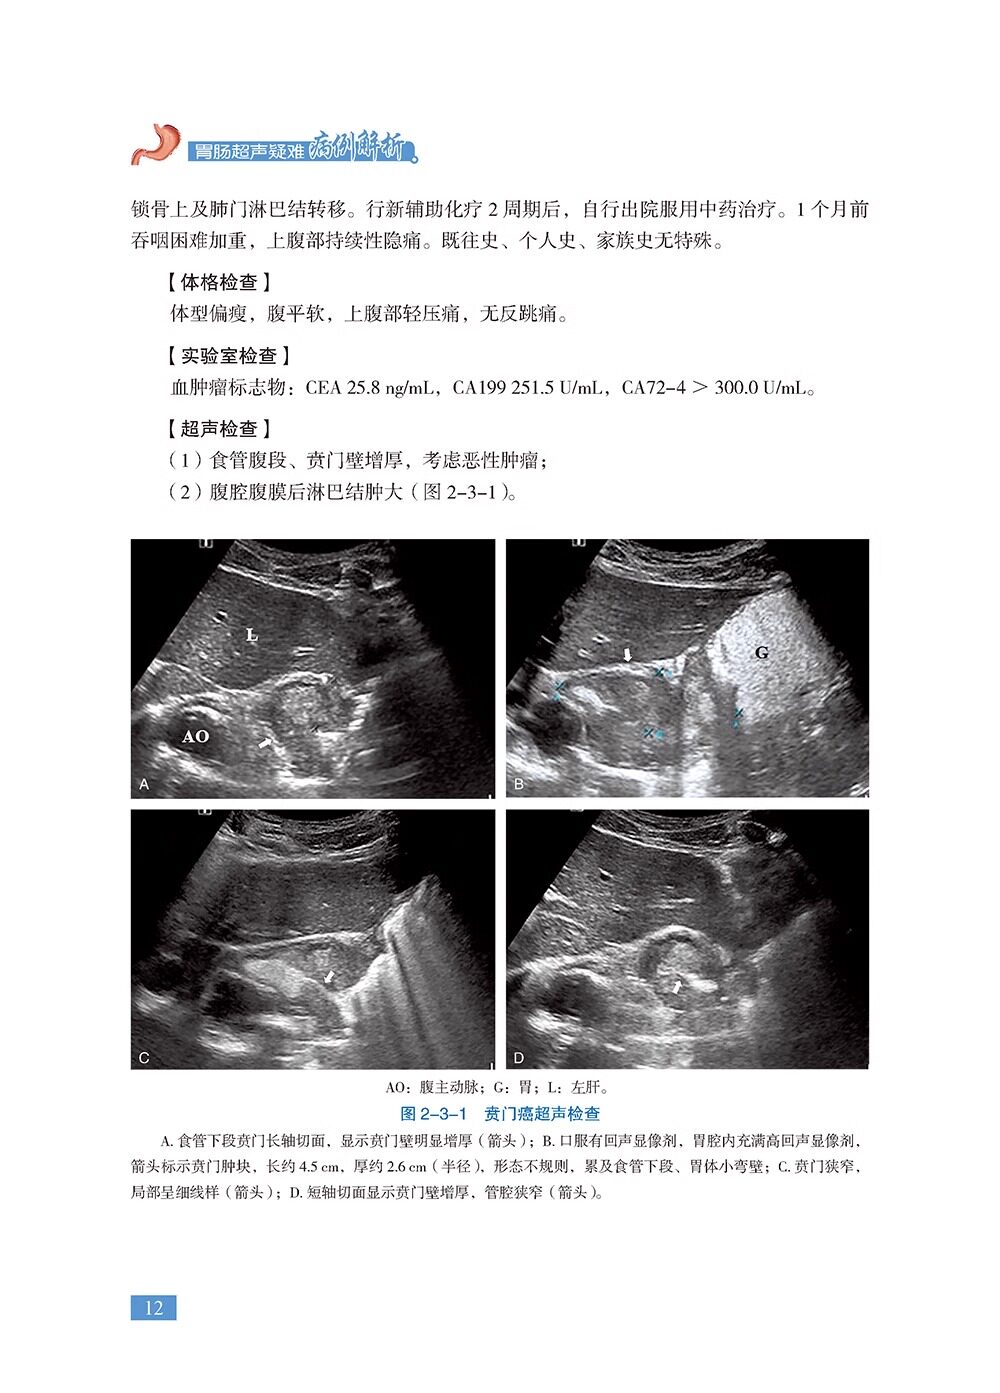

本书是《胃肠疾病超声诊断学》的姊妹篇,共18章,精心挑选了120个胃肠超声经典病例、疑难病例、罕见病例及误诊病例。涵盖各种胃肠道肿瘤、消化性溃疡、炎症性肠病、急腹症、先天异常、胃肠周围血管疾病等内容。每个病例从病史、体格检查、实验室检查、超声检查、其他影像检查、诊疗经过、病理诊断等方面进行详细阐述,并针对病例的超声特征及误诊原因等进行精准解析。全书精选了700余幅超声、CT、MRI、病理等图片,内容丰富、图文并茂,具有很强的实用性和指导性。适合各级超声医师及相关学科临床医师、医学院校师生阅读。